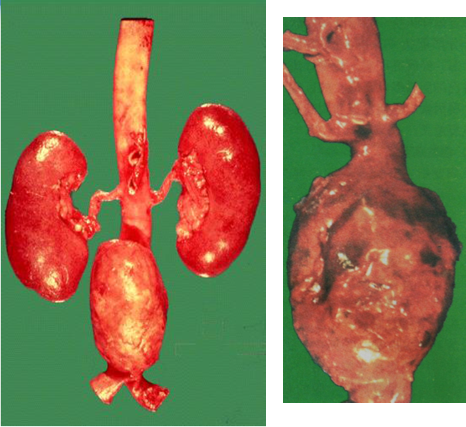

3.肾动脉粥样硬化

病变最常发生在肾动脉开口处及主干近侧端,亦可累及弓形动脉和叶间动脉,常引起顽固性肾血管性高血压;亦可因斑块内出血或血栓形成致肾组织梗死,梗死机化后形成较大瘢痕,使肾体积缩小,称为动脉粥样硬化性固缩肾。